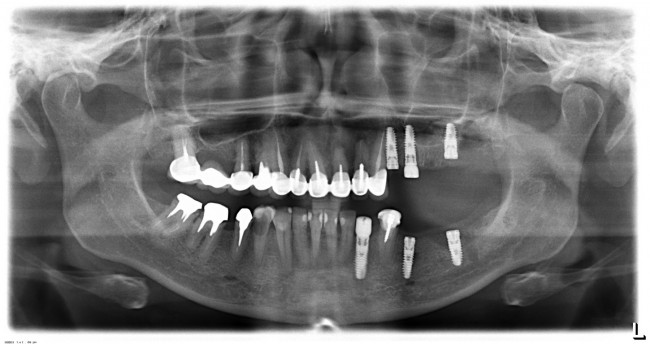

Вот пример. На этот раз, на снимках: пациентка, возрастом чуть больше сорока лет. После диагностики и необходимых исследований стало ясно, что необходимо хирургическое лечение во всех участках зубного ряда. В частности, удаление 13 зубов, включая ретинированный зуб мудрости, остеопластика на нижней челюсти и синуслифтинг, пластика слизистой и много чего еще.

У меня нет ипотеки и других долгов, поэтому я принимаю решение разбить весь объем хирургического лечения на четыре этапа — по одному в каждом из сегментов зубного ряда. И начинаю я… угадайте, с какого участка? Верно, с того, который уже не функционален из-за критического разрушения зубов — с левого нижнего:

Операция заняла всего 60 минут, послеоперационные явления были настолько незначительны, что пациентка чуть ли не через пару недель решилась на вторую операцию: